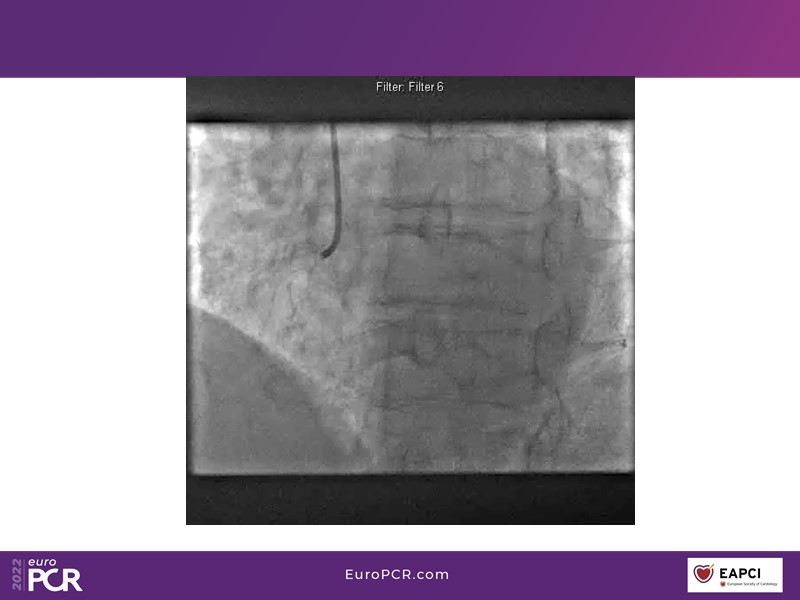

- To find out more about the application and mechanism of a sirolimus coated balloon for coronary artery disease treatment with case presentations in complex settings